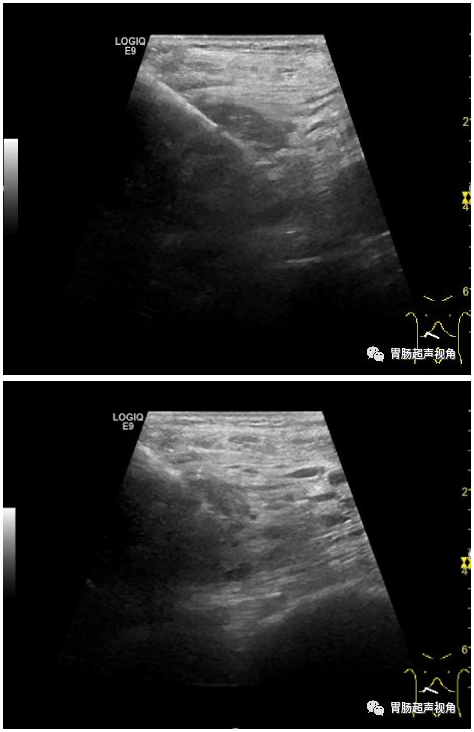

超声介入穿刺:

两次介入超声穿刺病理结果:

术中所见及标本:

患者行胰腺十二指肠切除、右半结肠切除术。术中于胰头钩突部至水平见一直径约8cm质硬肿块,界限不清,与横结肠系膜、大网膜及十二指肠系膜致密粘连。